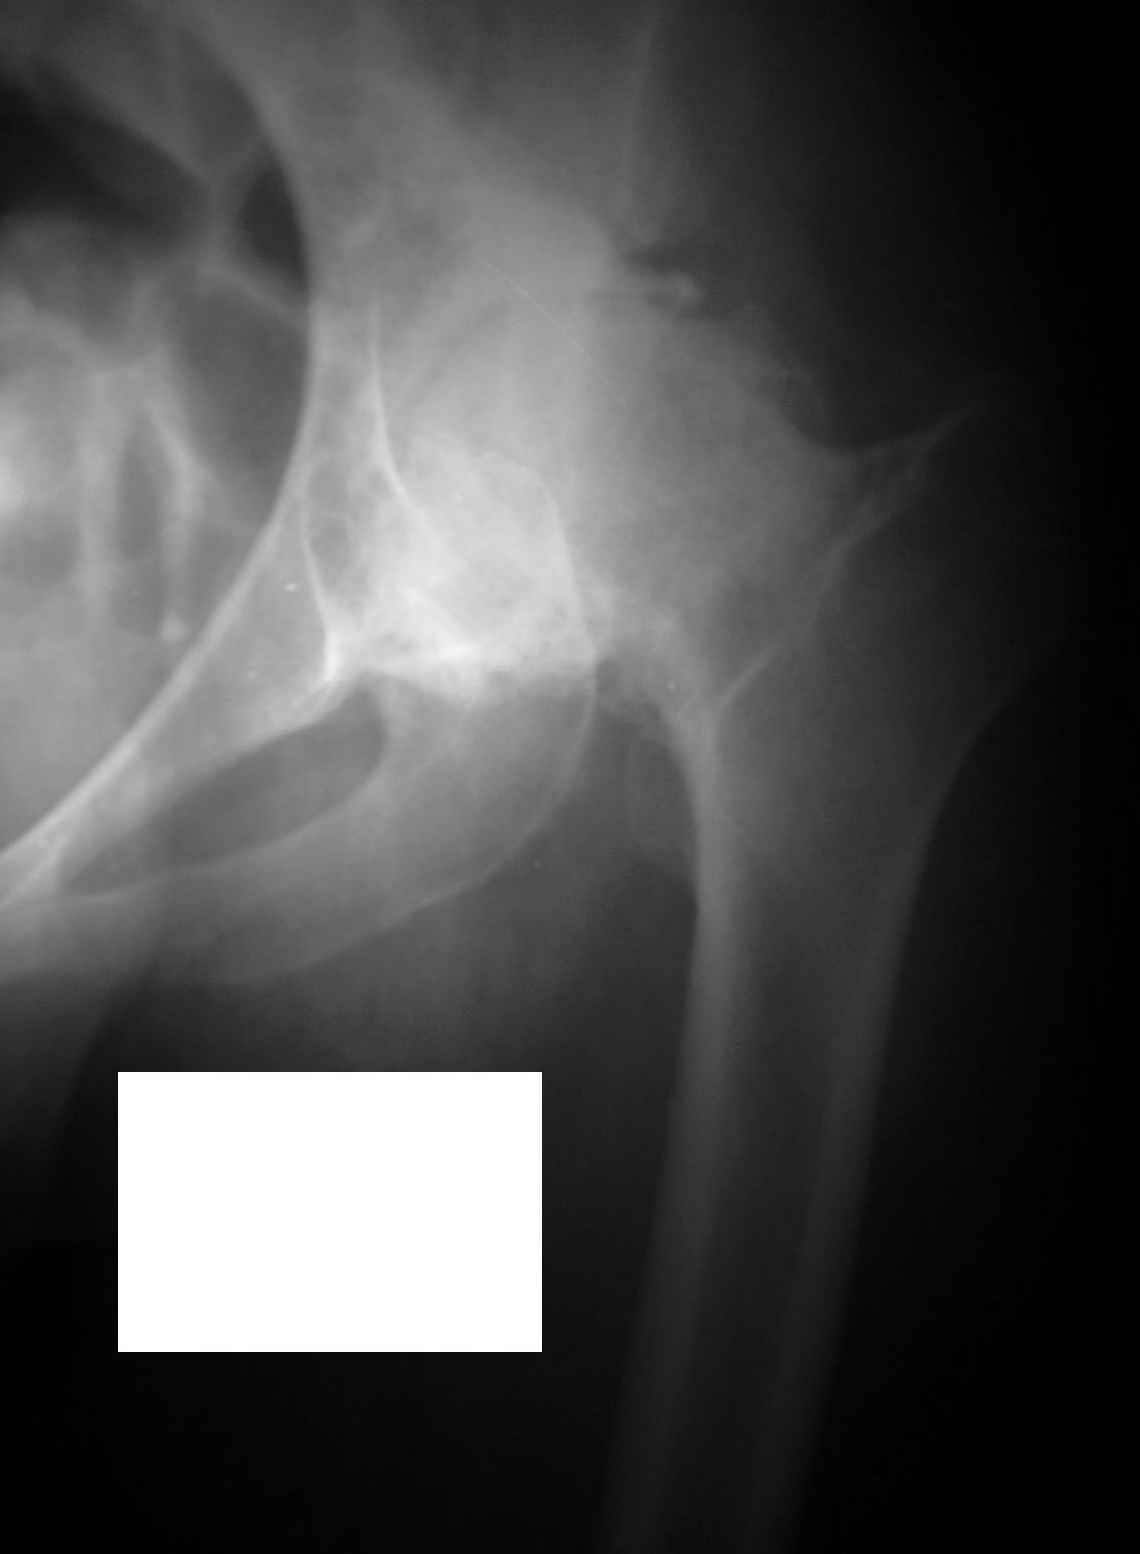

Извините, Анатолий, головка не выглядит потерянной, укорочение 5 см из-за порочного положения. Подход у молодой женщины я бы выбрал в зависимости от мобильности сустава.

На ригидном суставе межвертельная остеотомия для женщины мало привлекательна, но при гипомобильности, а тем более мобильности сустава вполне пригодна. И эффект от операции мы наблюдаем больше 10 лет и для последующего эндопротезирования трудности не велики, если остеотомию правильно спланировать и выполнить (проксимальный отдел бедра после остеотомии должен соответствовать нормальной анатомической геометрии). Привожу, что под рукой - Ртг 1997 ( даме 27 лет) и 2004 года. А моделей эндопротезов бесцементной фиксации для такой рентгеноантомической формы коксартроза действительно достаточно.

Кликните для загрузки файла Форум.jpg